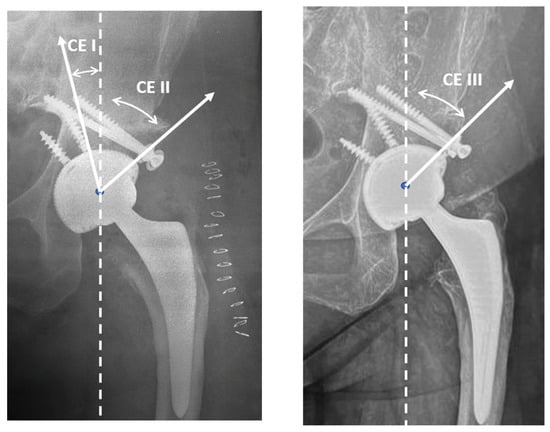

2.2. Radiological Assessment

3.2. Radiographic Results